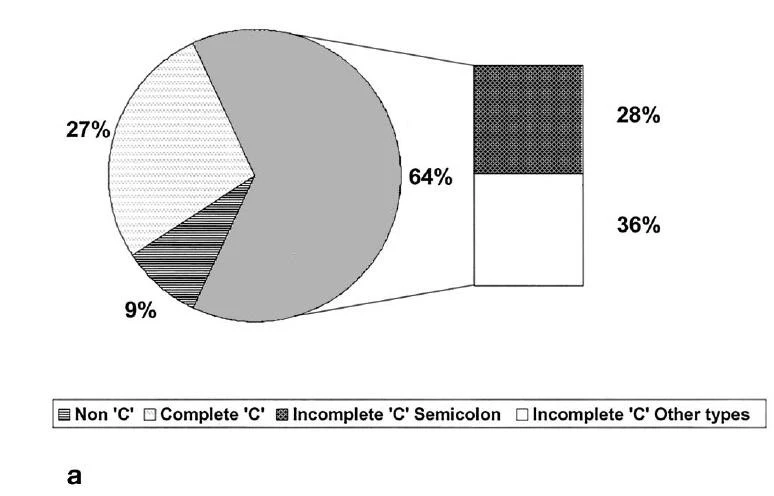

Theo một khảo sát trên 20 cases CS ,thì tỷ lệ : loại 1 là 27%,2+3 là 64%,loại 4 là 9%. Trong đó 95% là Răng 7 hàm dưới .Theo một số báo cáo khác thì CS cũng gặp trên R6 dưới,R4 dưới,R8 dưới,R6 trên,R7 trên.Lưu ý là phân loại này chỉ tính trên lỗ ống tủy ( orifices) tại sàn buồng tủy chứ còn nếu xuống theo từng lát cắt ngang ( cross – section) thì nó có thể biến từ dạng này sang dạng khác ( khi dính,khi lại tách rời !).